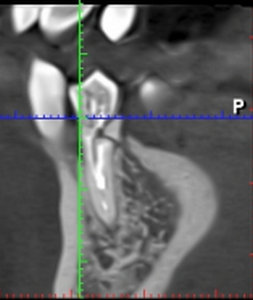

Зависит от того, насколько он треснул.

Если дефект распространился на корень зуба, то, однозначно, удалять.

Если корень целый, то необходимо извлечь штифт, изготовить культевую штифтовую вкладку и покрыть коронкой.